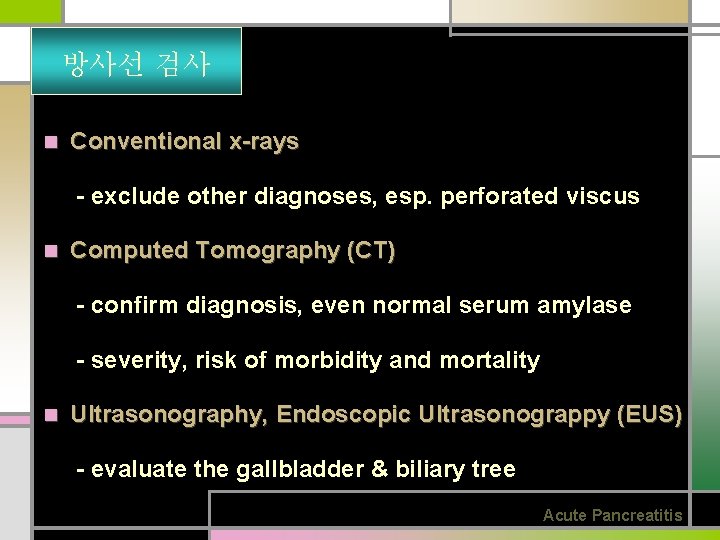

방사선 검사 n Conventional x-rays - exclude other diagnoses, esp. perforated viscus n Computed Tomography (CT) - confirm diagnosis, even normal serum amylase - severity, risk of morbidity and mortality n Ultrasonography, Endoscopic Ultrasonograppy (EUS) - evaluate the gallbladder & biliary tree Acute Pancreatitis